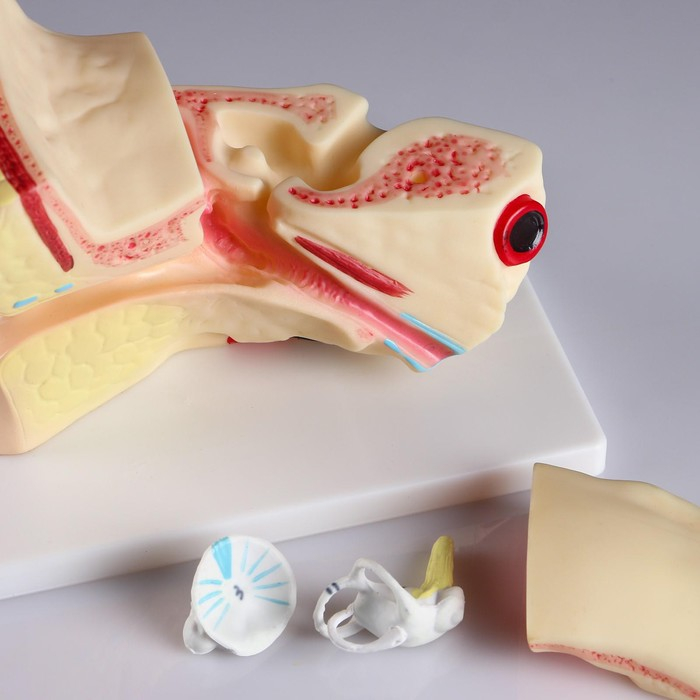

Анатомические модели